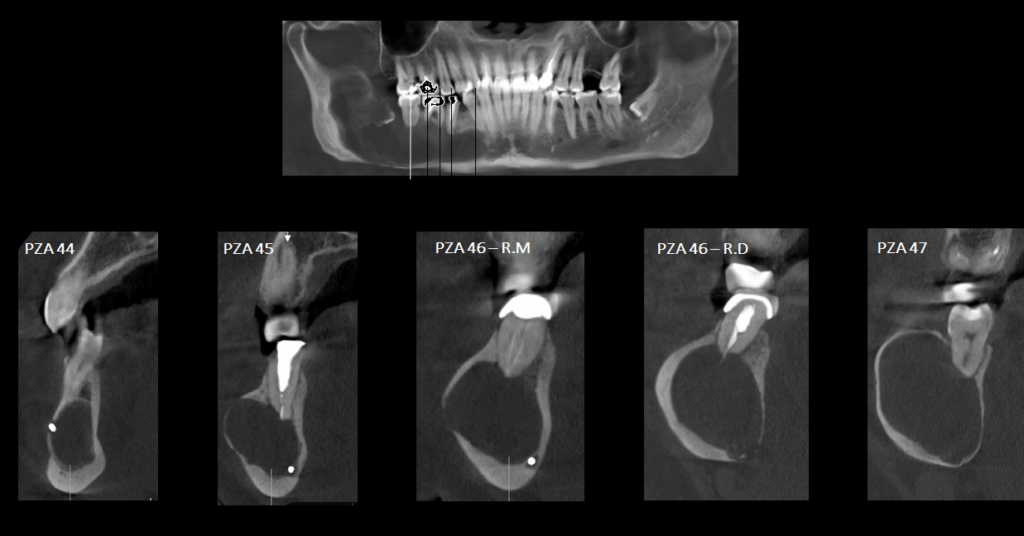

A la evaluación de la tomografía volumétrica (cone beam) bimaxilar en los cortes axiales (Figura 2), coronales, (Figura 3) y tangenciales (Figura 4) se observa imagen isodensa irregular, ubicado en cuerpo, ángulo y rama ascendente mandibular de lado derecho, que se extiende desde zona periapical mesial de pieza 44, hasta tercio medio de rama mandibular, y desde tercio superior (próximo a base de apófisis coronoides) hasta basal mandibular ocasionando expansión de tablas ósea, adelgazamiento de corticales y pérdida de continuidad de tabla vestibular en zona de pieza 45 y de tabla ósea lingual a en zona de pieza 46, 48 y rama mandibular. Además de producir el desplazamiento caudal y borramiento parcial de las corticales del canal mandibular; así mismo, se observó reacción periostal en tabla ósea vestibular (próxima a escotadura sigmoidea), ángulo mandibular y en basal mandibular de zona antegonial. Se pudo evidenciar tambien a la pieza 48 incluida y con reabsorción severa 48 dejando solo restos de esmalte.

CORTES TANGENCIALES